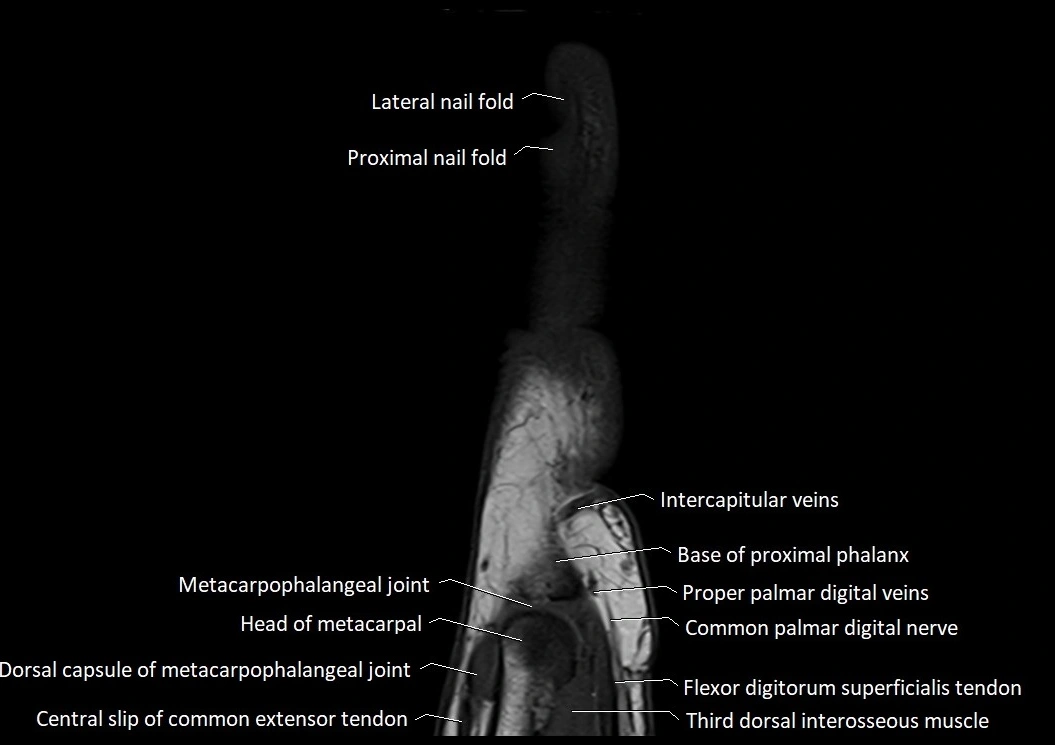

MRI images

image